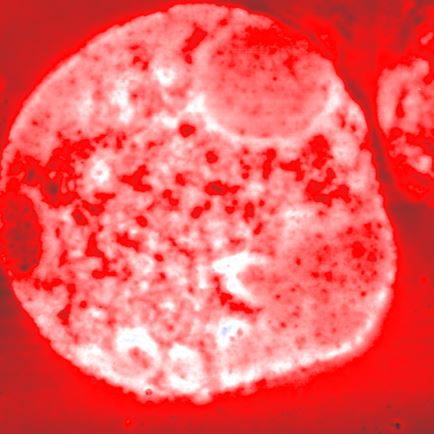

Blood cell

A blood cell was imaged using True Non-Contact™ mode to obtain surface topography.The scan image shows a circular cell with internal structural features, with height variations up to 211.6 nm.

- Peak-to-valley: 211.6 µm